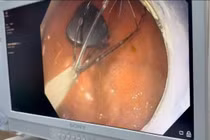

Trong quá trình phẫu thuật, các bác sĩ phát hiện nhiều viên nam châm nhỏ dính vào nhau thành một chuỗi, gây thủng ruột. Các bác sĩ phẫu thuật đã tiến hành lấy dị vật, khâu lỗ thủng và đặt dẫn lưu. Sau 4 ngày, bệnh nhi đã sinh hoạt bình thường, bắt đầu được tập ăn trở lại và dự kiến sẽ được ra viện trong một vài ngày tới.